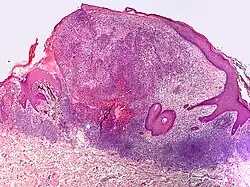

Small-cell melanoma

Small-cell melanoma, also known as melanoma with small nevus-like cells, is a cutaneous condition, a tumor that contains variably-sized, large nests of small melanocytes with hyperchromatic nuclei and prominent nucleoli.[1]

Small-cell melanoma, also known as melanoma with small nevus-like cells, is a cutaneous condition, a tumor that contains variably-sized, large nests of small melanocytes with hyperchromatic nuclei and prominent nucleoli.[1]